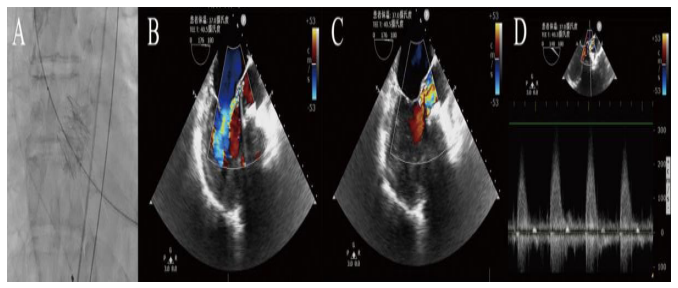

The patient was then scheduled for TAVI with the as- sistance of IABP and high dose of epinephrine and norepineph- rine. In the hybrid operating room (OR), his baseline HR was BP was 80/40 mmHg, and Sp02 (Fi02 50%) was 92%. General anesthesia was induced

with 2 mg midazolam, 20 pg sufentanyl and 50 mg ro. curonium, and then maintained with 1-1.5% sevoflurane. A 25- mm SAPIEN transcatheter heart valve (Ed. wards Lifesciences) was deployed successfully through a transapical approach with the guidance of cinefluoroscopic and TEE (Figure 2). Immediately after deployment of the valve, the patientdemonstrated significant hemodynamic improvement and the peak AV veloc. ity dropped from 12.33m/s to 3.2m/s, with epinephrine reduced from 0.3 to O, I gg/kg/min and norepinephrine was reduced from 0.8 to 0.3 gg/kg,fmin The surgery lasted 120 minutes, and the whole prcxedure was smooth and uneventful. IABP was used intraoperatively to assist circulation.

No adverse cardiac events, e.g, cardiac arrest or malignant arrhythmia, occurred in the OR.